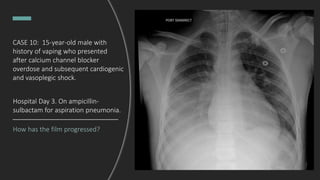

CASE 10: 15-year-old male with

history of vaping who presented

after calcium channel blocker

overdose and subsequent cardiogenic

and vasoplegic shock.

How has the film progressed?

Hospital Day 3. On ampicillin-

sulbactam for aspiration pneumonia.

Right parapneumonic effusion.